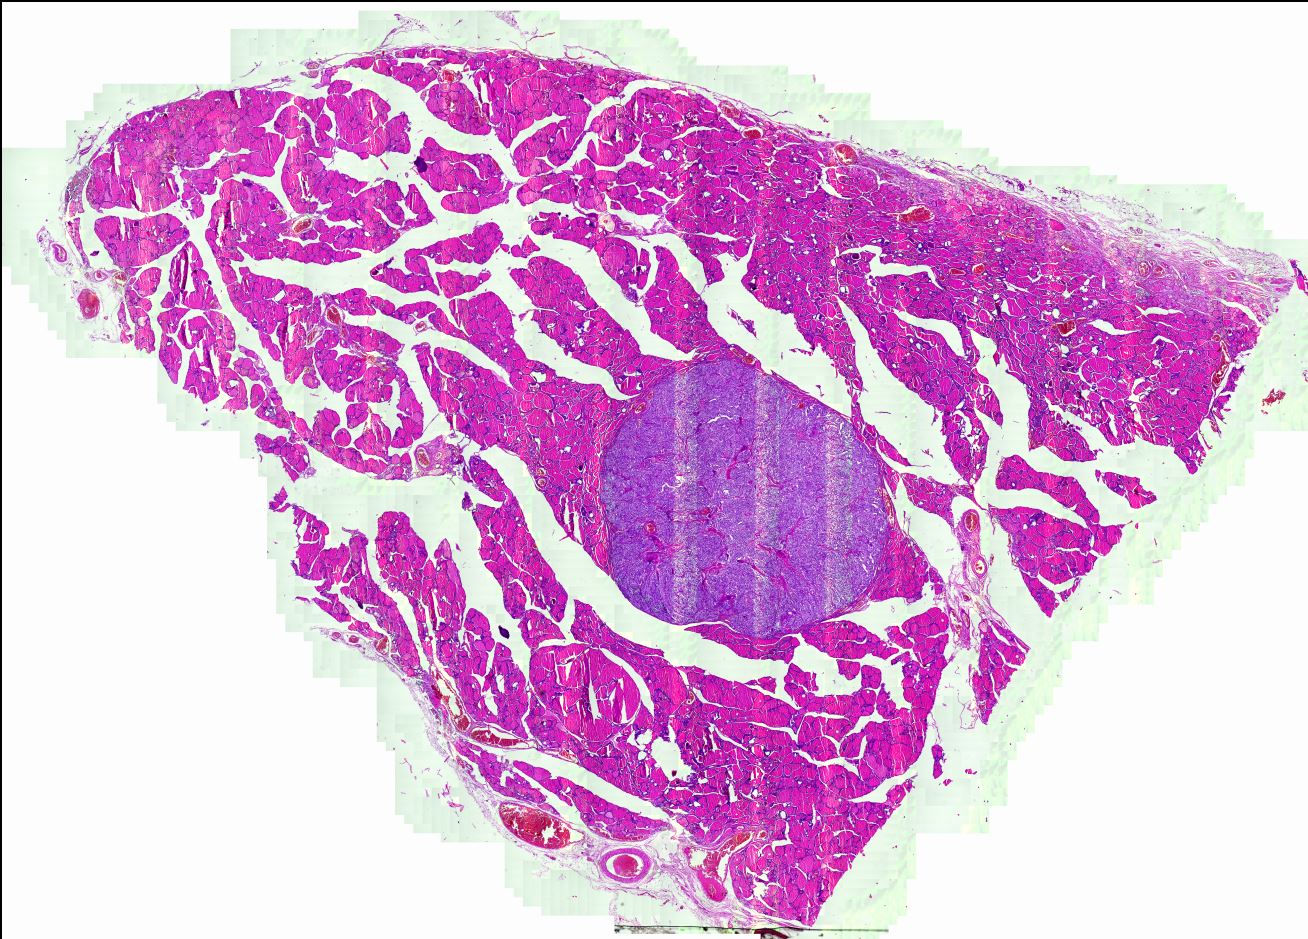

Cribriform-morular thyroid carcinoma Tiroidin nadir tümörü. Belirsiz papiller yapılar, moruller ve tiroglobulin yokluğu. Beta katanin ilişkili.

Cribriform-morular thyroid carcinoma, ikinci odak ile birlikte Çok sayıda odak içeren tümörde iki ayrı tümör odağı